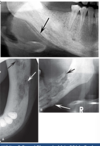

explain the steps in which this periapical periodontitis shown has occured

1) bacterial ingress via caries/ cracks . fractures / marginal gaps in restorations 2) reversible pulpitis ---> irriversible pulpitis ---> pulp necrosis ---> root canal system becomes infected 3) inflamm response happens 'periapical periodontitis' occurs to confine infection/ bacterial ingress 4) the body results in resorption, formation of granulation tissue (cysts may also occur) resulting in radiolucency 5) bone foramtion may also occur - may result in corticated (white) margin and/or general sclerosis of adjacent bone (to wall off infection)

what is shown on this picture?

periacpical granuloma